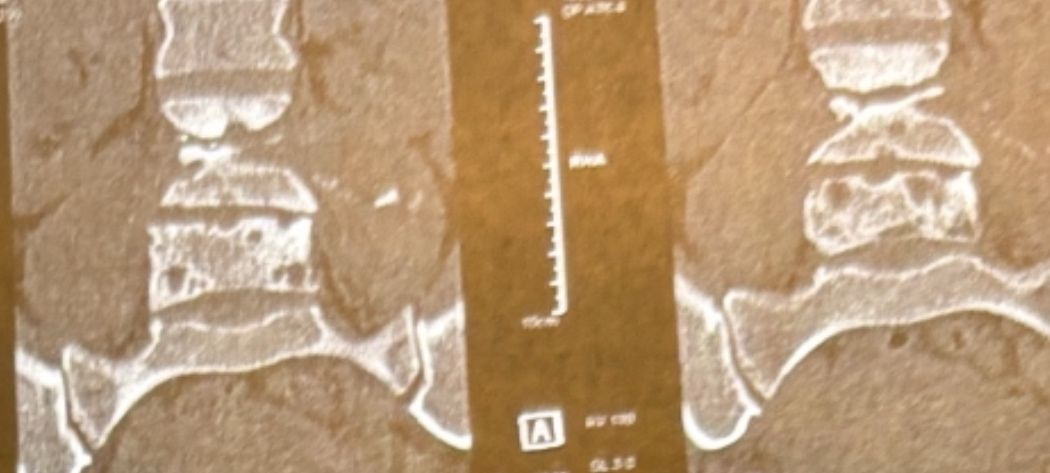

41 years old man presented to my clinic in October 2023 with acute and sever R neck pain with radicular pain to his R upper extremity along C6 dematom since 2 weeks ago. Examination didn’t show any upper motor signs. Was suggested urgent surgery

I ordered EMG/ NCV : showed mild R C6, C7 irritation without any active axonal loss

In his MRI was reported R. para R. IVF Massive extrusion. I decided to control his pain and manage this patient with reevaluation of patient every other session. For 5 sessions i just used acupuncture and laser and IFC and mild adjustments to his R. T3-T7 and mild arthosteem to above and below involved segment. Cervical adjustment considered contraindicated for this patient. From session 6th- 8th i started to use mild/gentle cervical decompression. He used soft cervical collar all the time. His pain decreased by 80 percent

I gave him cervical traction pump to be used 3-5 times per day at home for the next 3 months and i released the patient. He was evaluated every week once for one month and after that every 2 weeks. After 3 month I repeated MRI. Size of the herniated disc was reduced greater than 50 percent. Asked him to do another mri in 6 months

In general: Precise selection of the patients, examination,diagnosis, plan of management, reevaluation and treatment can be done by doctors of chiropractic for the patients with spinal disc herniation and stenosis Moreover giving reasonable time to these kind of patients under direct supervision by their chiropractic doctors can prevent unnecessary surgery. Proper selection of these kind of patients is another important fact that can be done precisely by chiropractors.

MRIs before and after proper management of this patient: